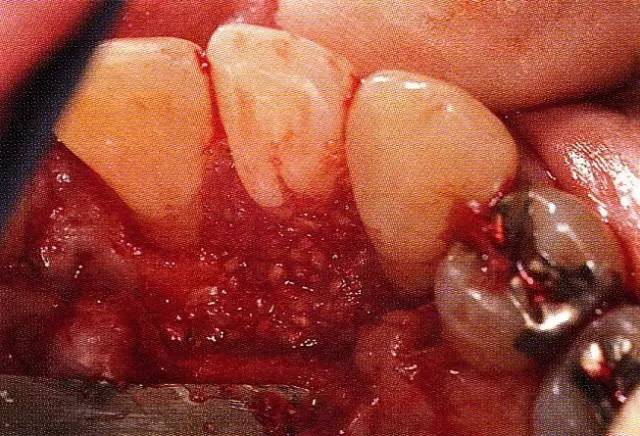

▲圖8-7  再生療法后11周,將非吸收性膜去除。與術(shù)前的缺損部相比較,可看到形成了新生肉芽組織。

640.webp (13).jpg